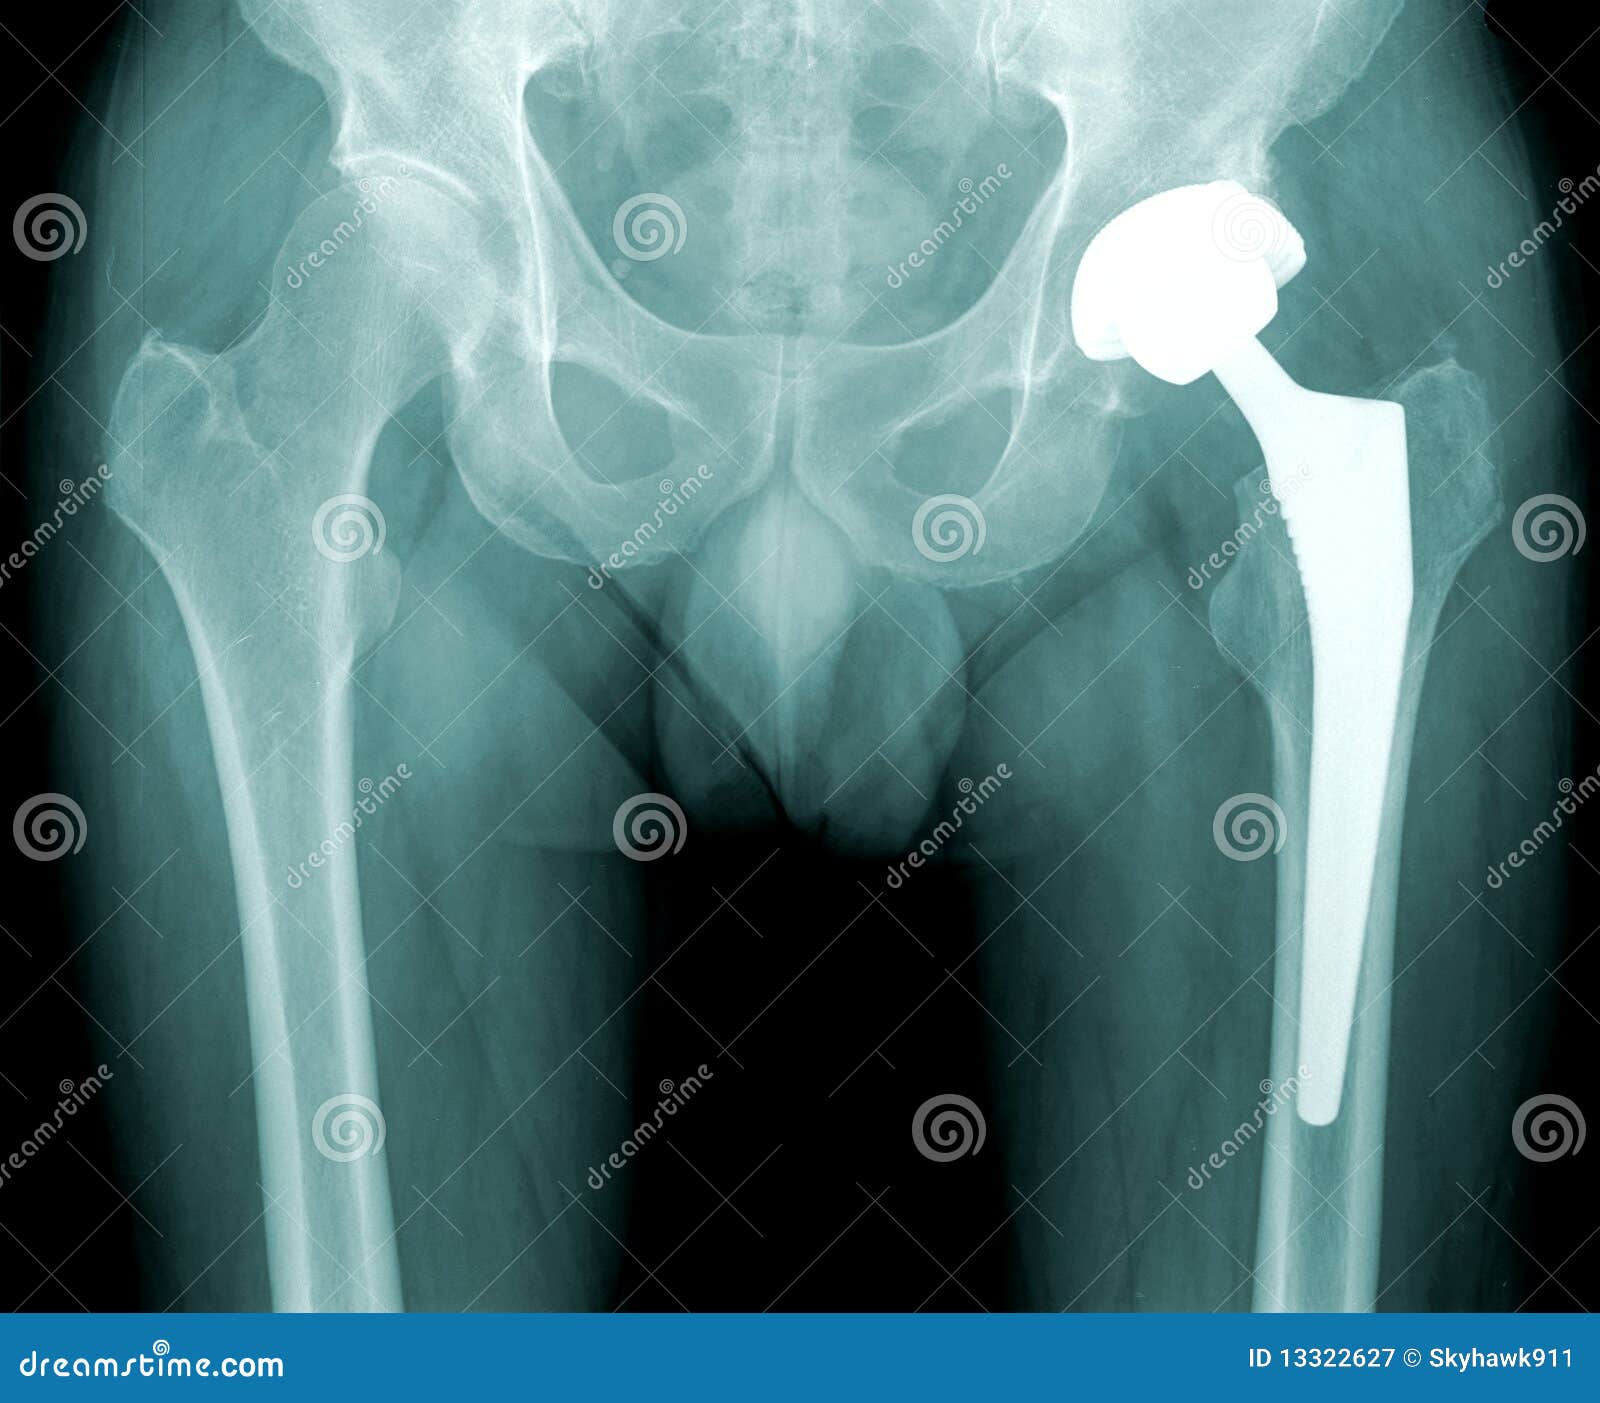

Hip X-ray With Replacement Of The Joint Royalty-Free Stock Photography ...

Hip implants have revolutionized the field of orthopedics, providing relief and improved mobility for countless individuals suffering from hip joint issues. One of the critical aspects of managing hip implants is the use of hip implant X-ray imaging. This diagnostic tool plays a pivotal role in the pre-operative planning, post-operative monitoring, and long-term management of hip implants. Understanding the importance and process of hip implant X-ray imaging can help patients and healthcare providers make informed decisions.

Hip implant X-ray imaging is an essential diagnostic tool used to evaluate the condition of the hip joint and the implant itself. It provides detailed images that help orthopedic surgeons assess the alignment, positioning, and integrity of the implant. This information is crucial for both pre-operative planning and post-operative monitoring.